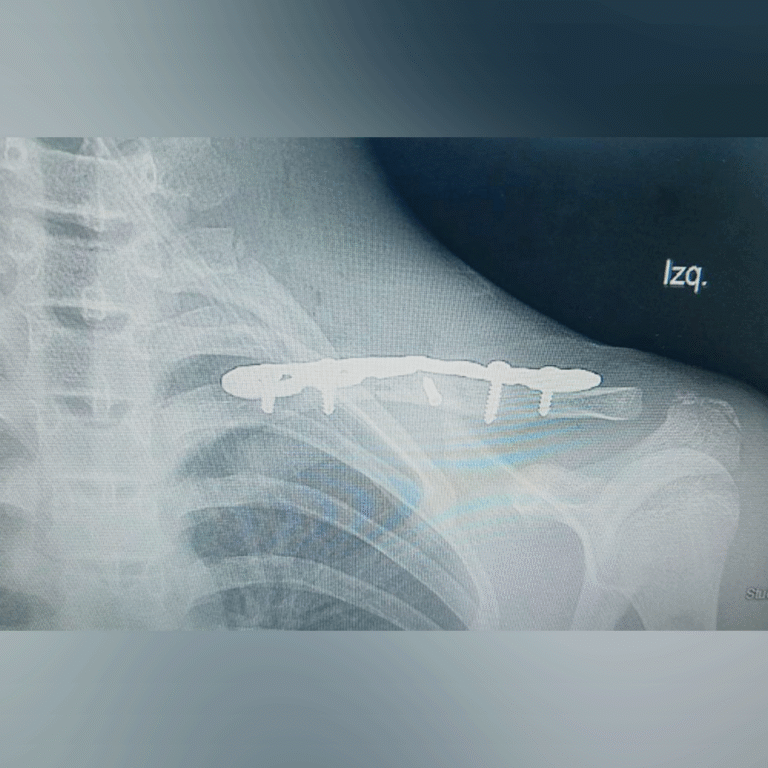

🩺 Resultados que transforman vidas. Descubre cómo hemos devuelto la movilidad y eliminado el dolor de mis pacientes mediante tratamientos efectivos.